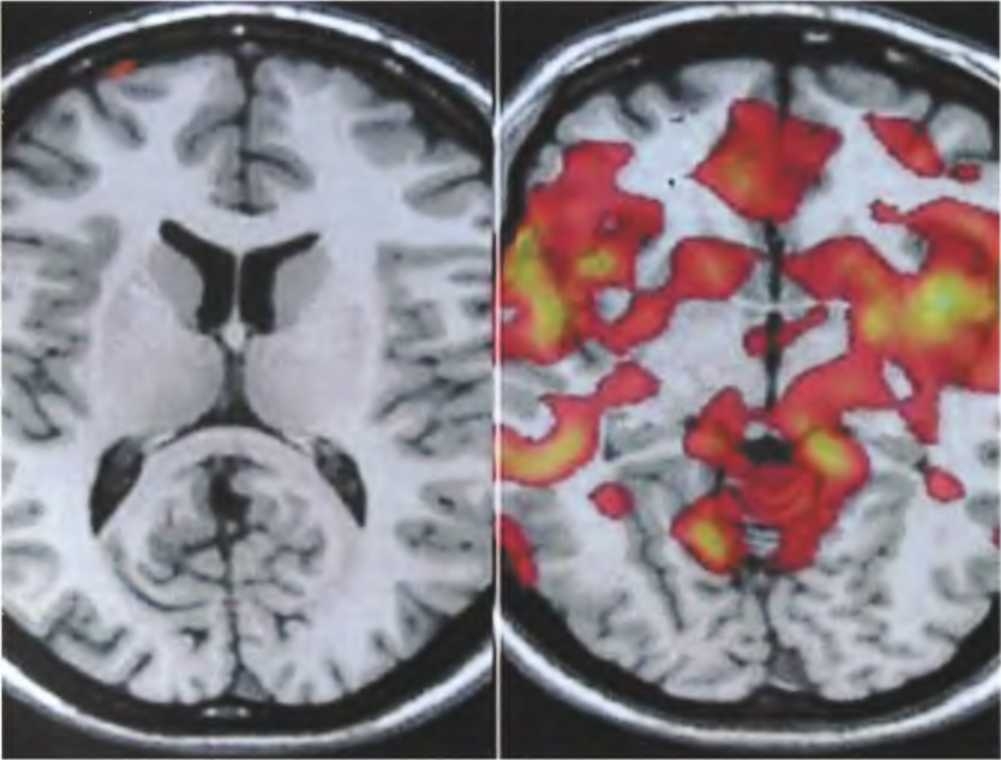

На приведенных здесь иллюстрациях (если верить создателям программы, с помощью которой они обработаны) видна разница между мозгом человека, говорящего правду (слева), и человека, который лжет (справа). Полагают, что дополнительная активность, наблюдаемая во втором случае, связана с дополнительными когнитивными усилиями, которые требуются для подавления естественного стремления рассказывать все как есть и для измышления правдоподобной лжи. Такие результаты позволяют предположить, что по умолчанию наш мозг настроен на то, чтобы говорить правду, а ложь представляет собой сложное усовершенствование, требующее постоянной доработки.

“Детекторы лжи”, основанные на методе ФМРТ, уже находят судебное применение, и, возможно, рано или поздно они полностью вытеснят полиграфы. Однако их использование по-прежнему вызывает массу споров, и некоторые люди настаивают на том, что лабораторные условия, в которых тестировались такие детекторы, не имеют никакого или почти никакого отношения к сложным, запутанным случаям из реальной жизни. Тем не менее стоит помнить о том, что традиционные способы определять, говорит человек правду или лжет (интуиция, суждения сторонних наблюдателей и полиграф), также довольно ненадежны [см.: Sip, К. Е., Roepstorff, A., McGregor, W., and C.D. Frith Detecting deception: the scope and limits // Trends in Cognitive Sciences 12: 2 (2008), pp. 48-53].